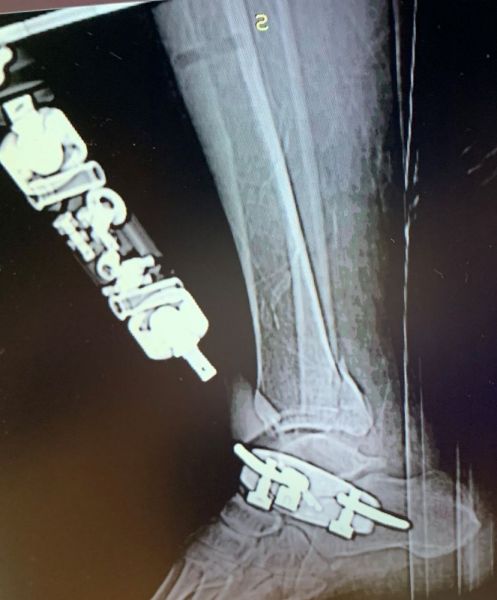

4. Fracture-dislocation of the right ankle in a 50-year-old male.

Treatment: 1st step, external fixation. 2nd step after 14 days, removal the external fixator and at the same time open reduction internal fixation (ORIF)

I. Before surgery, lateral x-ray shows the fracture of tibia and of lateral malleolus II. Post-surgery 1st step, the external fixator III. 2nd step, removal the external fixator and at the same time ORIF